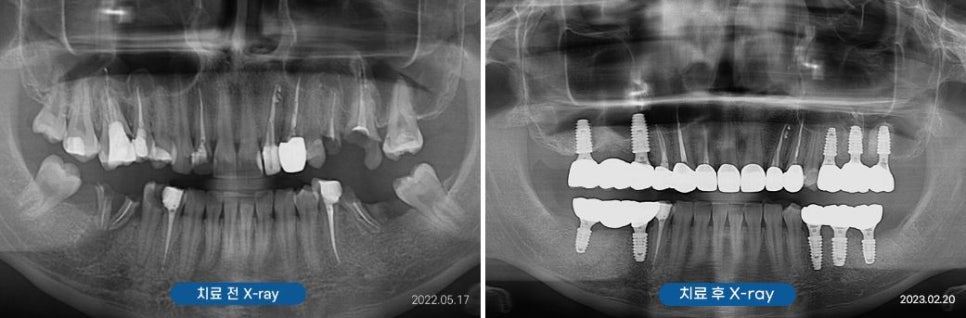

조금 더 정확한 검사를 하기 위해

X-ray(Panorama)와

구강포토를 촬영하였습니다.

아래쪽 양쪽 어금니와

위쪽 사진 기준 왼쪽 어금니가

많이 손상되어

치아머리가 더의 보이지 않았는데요.

않타깝게도 부러진 치아의 치질이

거의 없는 상태였기에

치아를 살릴 수 없어

양쪽 위 아래 어금니 임플란트로

계획을 세우게 되었습니다.

부러진 어금니로 인해

많이 불편했었는데

임플란트 후 이제 편안하게

식사를 할 수 있어

건강도 더 좋아진 것 같아요!